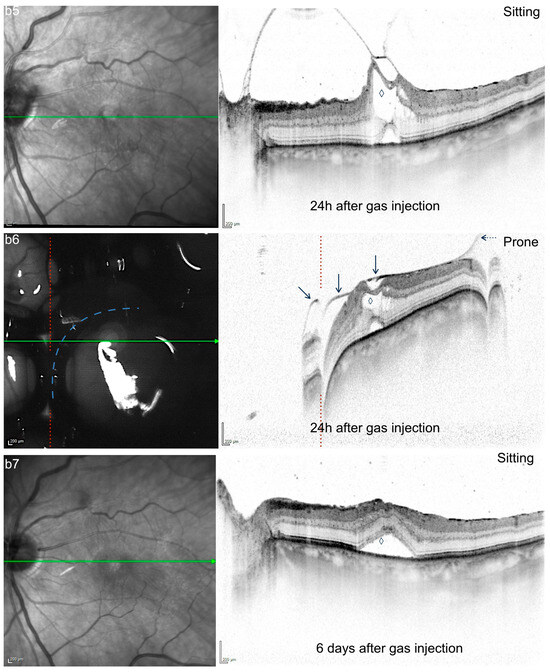

Mechanisms of Gas-Induced Posterior Vitreous Detachment: A Look Behind the Bubble Using Optical Coherence Tomography in Prone Position

Objectives: We aimed to visualize the interaction of intravitreal gas with the adjacent vitreomacular interface by using prone position (PP) SD-OCT and suggest possible mechanisms of action behind gas-induced posterior vitreous detachment (PVD) in pneumatic vitreolysis (PV). Methods: This was a descriptive–interpretative morphological [...] Read more.

Objectives: We aimed to visualize the interaction of intravitreal gas with the adjacent vitreomacular interface by using prone position (PP) SD-OCT and suggest possible mechanisms of action behind gas-induced posterior vitreous detachment (PVD) in pneumatic vitreolysis (PV). Methods: This was a descriptive–interpretative morphological study. Spectral domain OCT imaging in PP was carried out using a flexible scanning module (SD-OCT-Flex, Heidelberg Engineering) originally designed for bedside imaging. Routine imaging in sitting position was carried out using a regular SD-OCT-device (Heidelberg Engineering). Patients with symptomatic vitreomacular traction (VMT) scheduled for PV with perfluoropropane (C3F8, 0.3 mL) received both sitting and PP imaging immediately before and at regular follow-up visits during the first 3 post-procedural weeks, beginning 3 h after PV. Imaging was reviewed for positional changes of the gas bubble, posterior hyaloid membrane (PHM), VMT configuration, and retrohyaloidal fluid (RHF). Results: Three consecutive patients with VMT were included (age: 79, 80, 82 years). Before the procedure, no positional alterations were detected. After the intravitreal injection of gas, PP allowed for the precise discrimination of the PHM and the posterior border of the gas bubble. In contrast to regular SD-OCT in sitting position, PP imaging showed a flattened VMT by the gas bubble with consecutive displacement of RHF from the macular region to the midperiphery. Conclusions: This exploratory study describes PP imaging as a tool for the assessment of the morphologic dynamics between the posterior hyaloid membrane, retina, and gas bubble in pneumatic vitreolysis. PP in pneumatic vitreolysis causes the gas bubble to flatten the VMT and to push retrohyaloidal fluid to the midperiphery, possibly allowing for the release of persistent vitreoretinal adhesions and consequent PVD induction. Full article